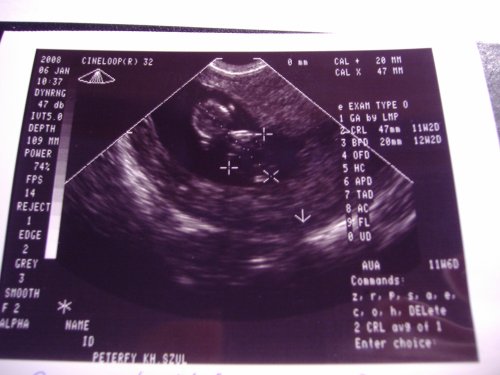

Teszek nektek képet én is már elég rég tettem!